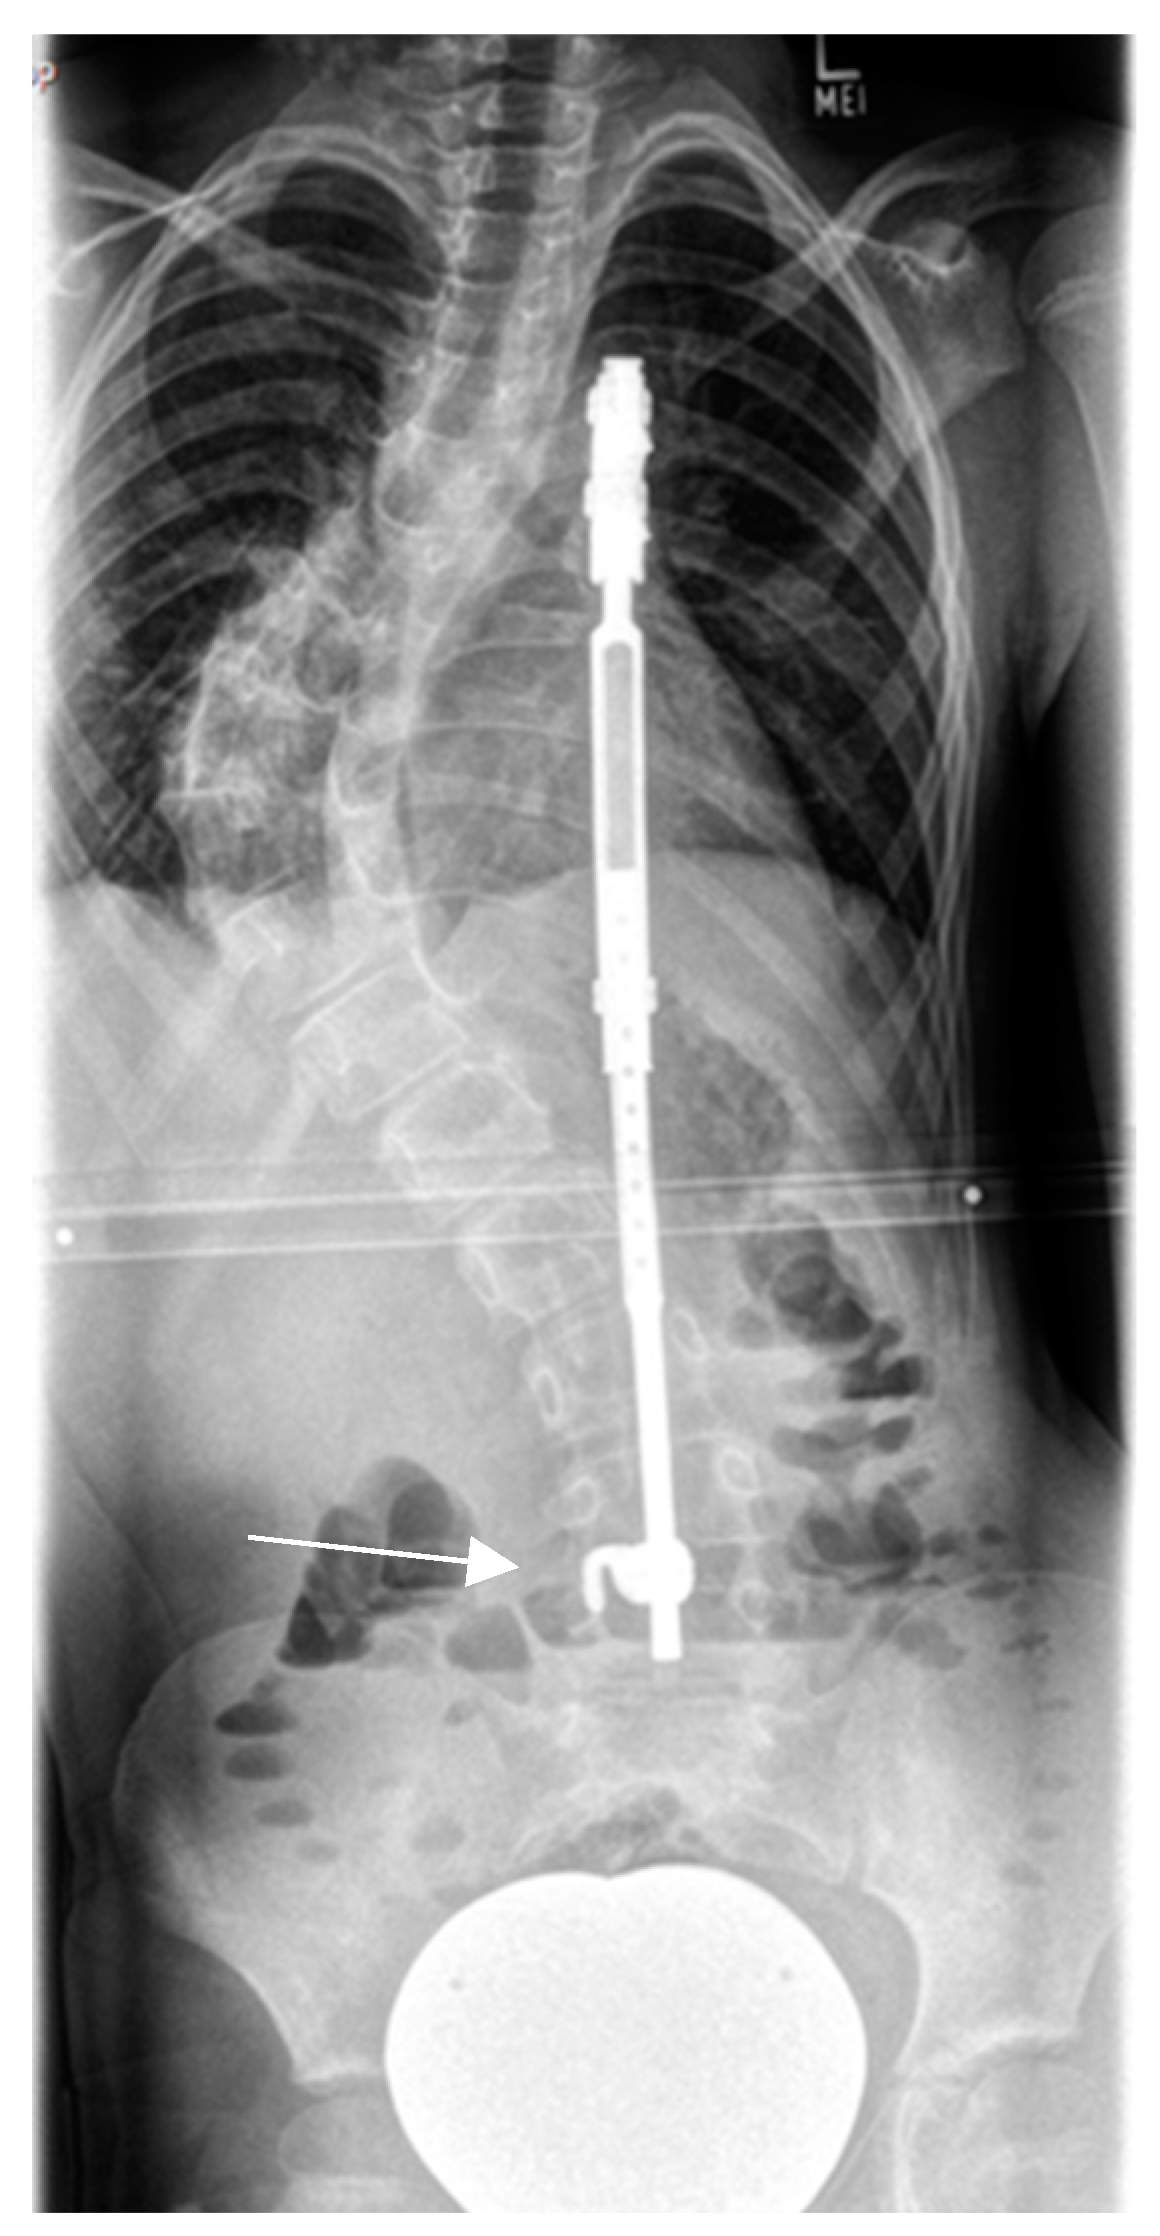

4.2.1. “Early Onset Spinal Deformity”

5.2.1. Growth-Preserving Techniques